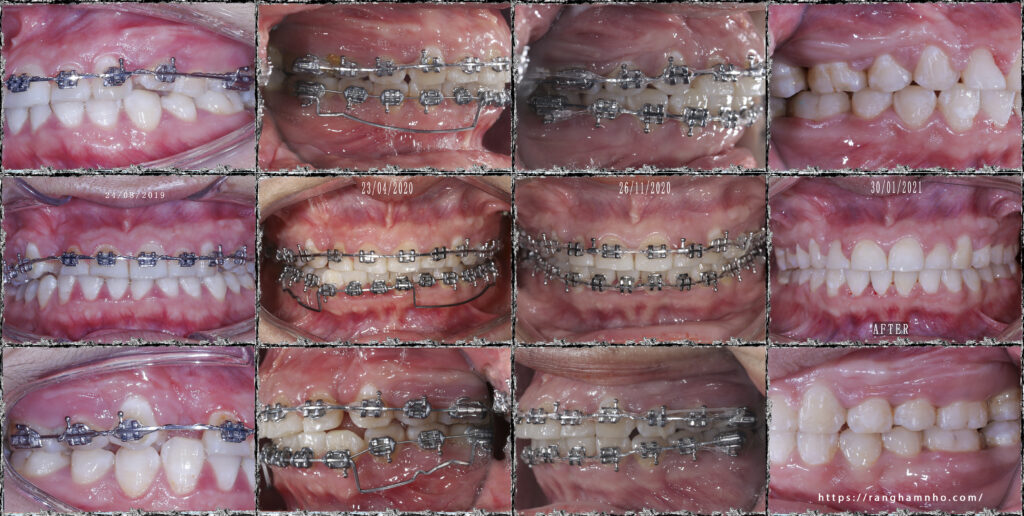

Trước điều trị: BN đã điều trị 2 năm tại 1 cơ sở nha khoa khác, và kết quả là, còn khoảng, răng còn xoay, khớp cắn chưa ổn định. R13 đáng phải giữ lại thì đã bị nhổ đi.

Phương án, ké di gần răng 4 về thay thế vị trí răng 3, xoay lại để làm đều nhóm răng cửa hàm dưới, bẻ torque để răng cửa trên đỡ chìa.

Kết quả: sau 1.5 năm điều trị, BN thoát niềng với các tiêu chỉ hoàn thành.